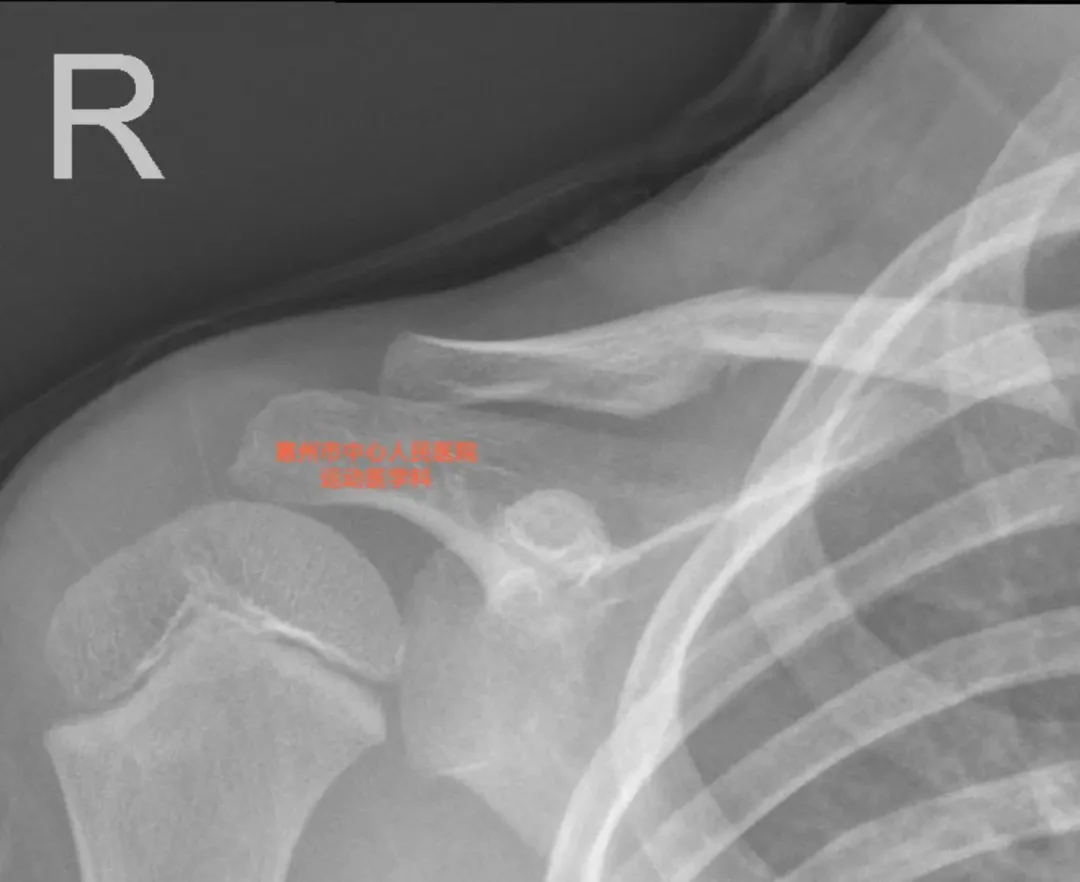

一拍片发现是锁骨骨折,看着骨折端稍有移位,但是总体位置良好。

家长问做不做手术?骨折现在已经不是我的主要专业范畴,但是做了这么多年骨科医生,我是没有做过这种情况的儿童锁骨骨折手术,我直觉是不需要手术,出于严谨,把片子发给了做儿童骨折的同事,答复是固定就好,然后我便告诉家长,悬吊、固定一下就好了,每2周复查一下x线片评估移位、短缩情况。